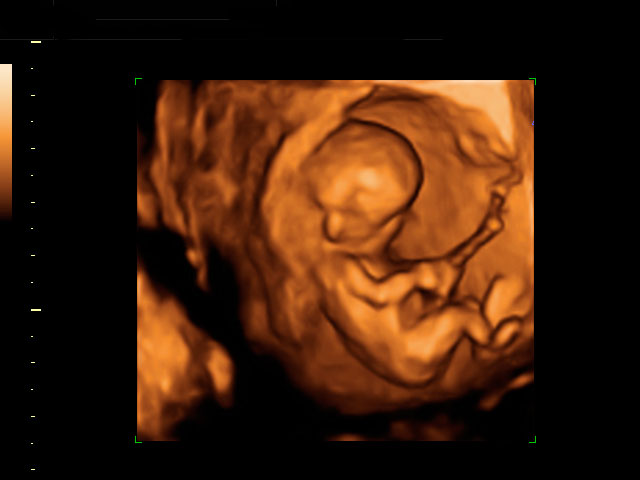

Ecografía Embarazo 2D y 3D - SEMANA 12